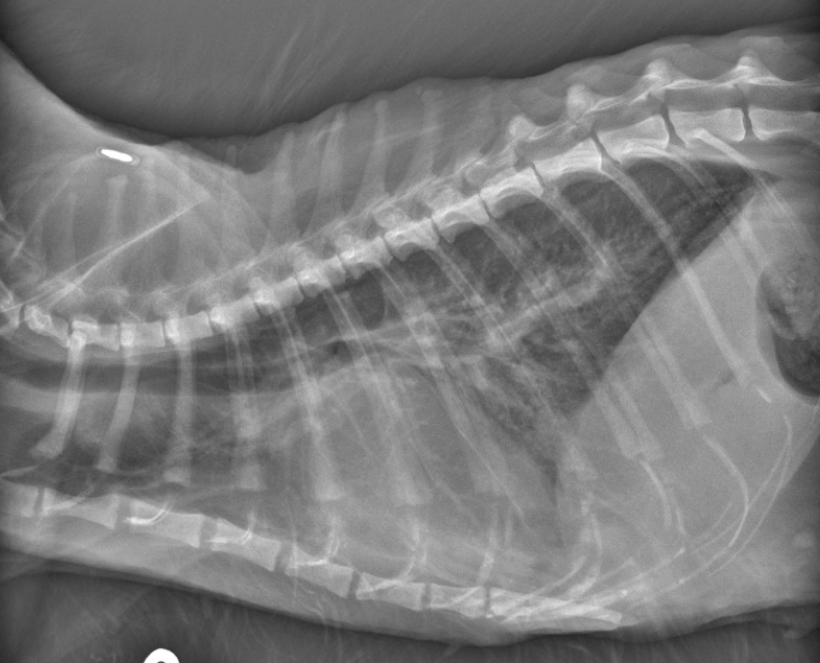

Cat - what sided HF is this

Dog - what sided heart failure is this

LHF

Cat- what sided heart failure